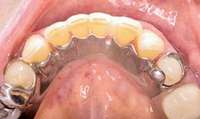

Bisphosphonate-related osteonecrosis of the jaws (BRONJ) is characterized by the presence of exposed bone in the oral cavity for more than 8 weeks in a patient who has been taking bisphosphonates and who has not had any radiation therapy in the oral cavity3 (Figure 1). The risk of BRONJ from the use of oral bisphosphonates is very low, currently about 1%.8 Most researchers believe this incidence is so low because it takes many years for the drug to saturate the bone. Most cases of BRONJ from oral bisphosphonates occur after at least 3 years of drug use.9 However, a recent study by Cartsos et al of over 700,000 medical claims found no increased incidence of inflammatory conditions, including osteonecrosis.10

Figure 1 Exposed bone in the mandibular jaw that is characteristic of BRONJ. Photo courtesy of Robert Marx, DDS.